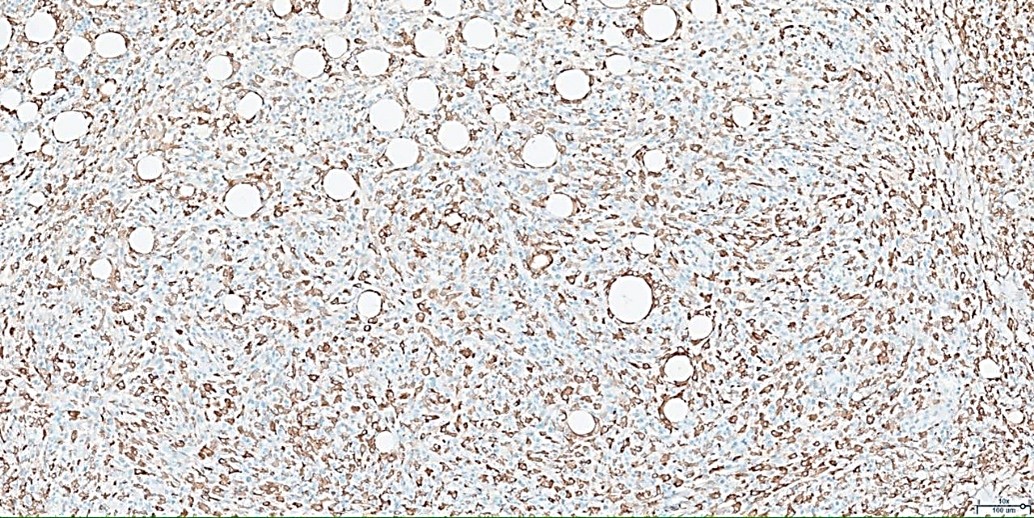

Histopathological examination revealed a non-circumscribed proliferation of large cells with marked nuclear pleomorphism, prominent nucleoli, and abundant clear cytoplasm, with numerous mitotic figures (Figure 3). Immunohistochemistry showed strong and diffuse expression of CD30 in atypical cells (Figure 4), and positivity for granzyme B, CD2, CD4, and CD25 in atypical T-cells (Figure 5). Numerous intermingled histiocytes were positive for CD68 and CD163, but negative in the atypical cells (Figures 6 and 7). ALK1 was negative in lymphoid cells (Figure 8). These findings supported the diagnosis of primary cutaneous anaplastic large cell lymphoma. Laboratory and PET-CT evaluation showed no extracutaneous disease. Localized electron beam radiotherapy was performed.

Figure 7: Immunohistochemistry for CD163 (10x): Positive in histiocytes, negative in atypical cells.